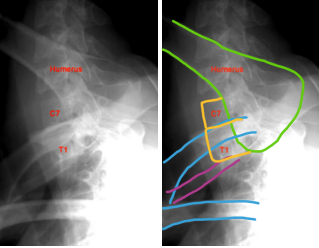

4. Nadador:

* Quando não é possível visualizar C7 na incidência

de perfil

Obs: hoje em dia é pouco utilizada

A

Verde: úmero

Azul: clavículas

Roxo: 1a costela

Amarelo: vértebras